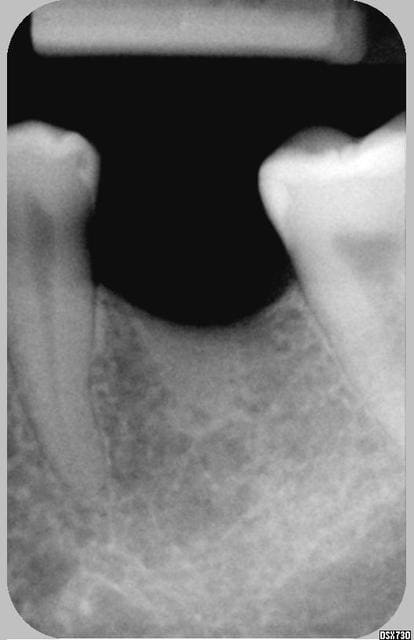

J'aimerai avoir votre avis sur ce cas (implant niveau 46).

L'image préop montrait déja une zone légèrement radioclaire.

celle-ci s'est "éclairci" sur le cliché à 3 mois, et est stable sur celui à 4 mois.

Image radioclaire et implant totalement immobile.

Six mois aprés la pose de la prothèse , implant toujours parfaitement immobile mais extériorisation vestibulaire d'une lésion de type granulomateuse.

Pour l'implant de rapeladent, je dirais que ça sent pas bon.

Fait un test au froid de la 45 pour voir si ton axe de forage n'a pas touché le paquet vasculonerveux de cette dent, ce qui pourrait expliquer effectivement la nécrose.

D'apres mon experience,lorsque tu as une image au tiers ou a "l'apex" de l'implant,et donc impossibilite de nettoyer,meme si l'implant semble solide (parceque qq mm du pas de vis sont osteointegres),eh bien le pronostique est plus que reserve.

L'image sombre autour de l'implant est comme une nuage noir qui préfigure l'orage... la "5" m'inquiète...